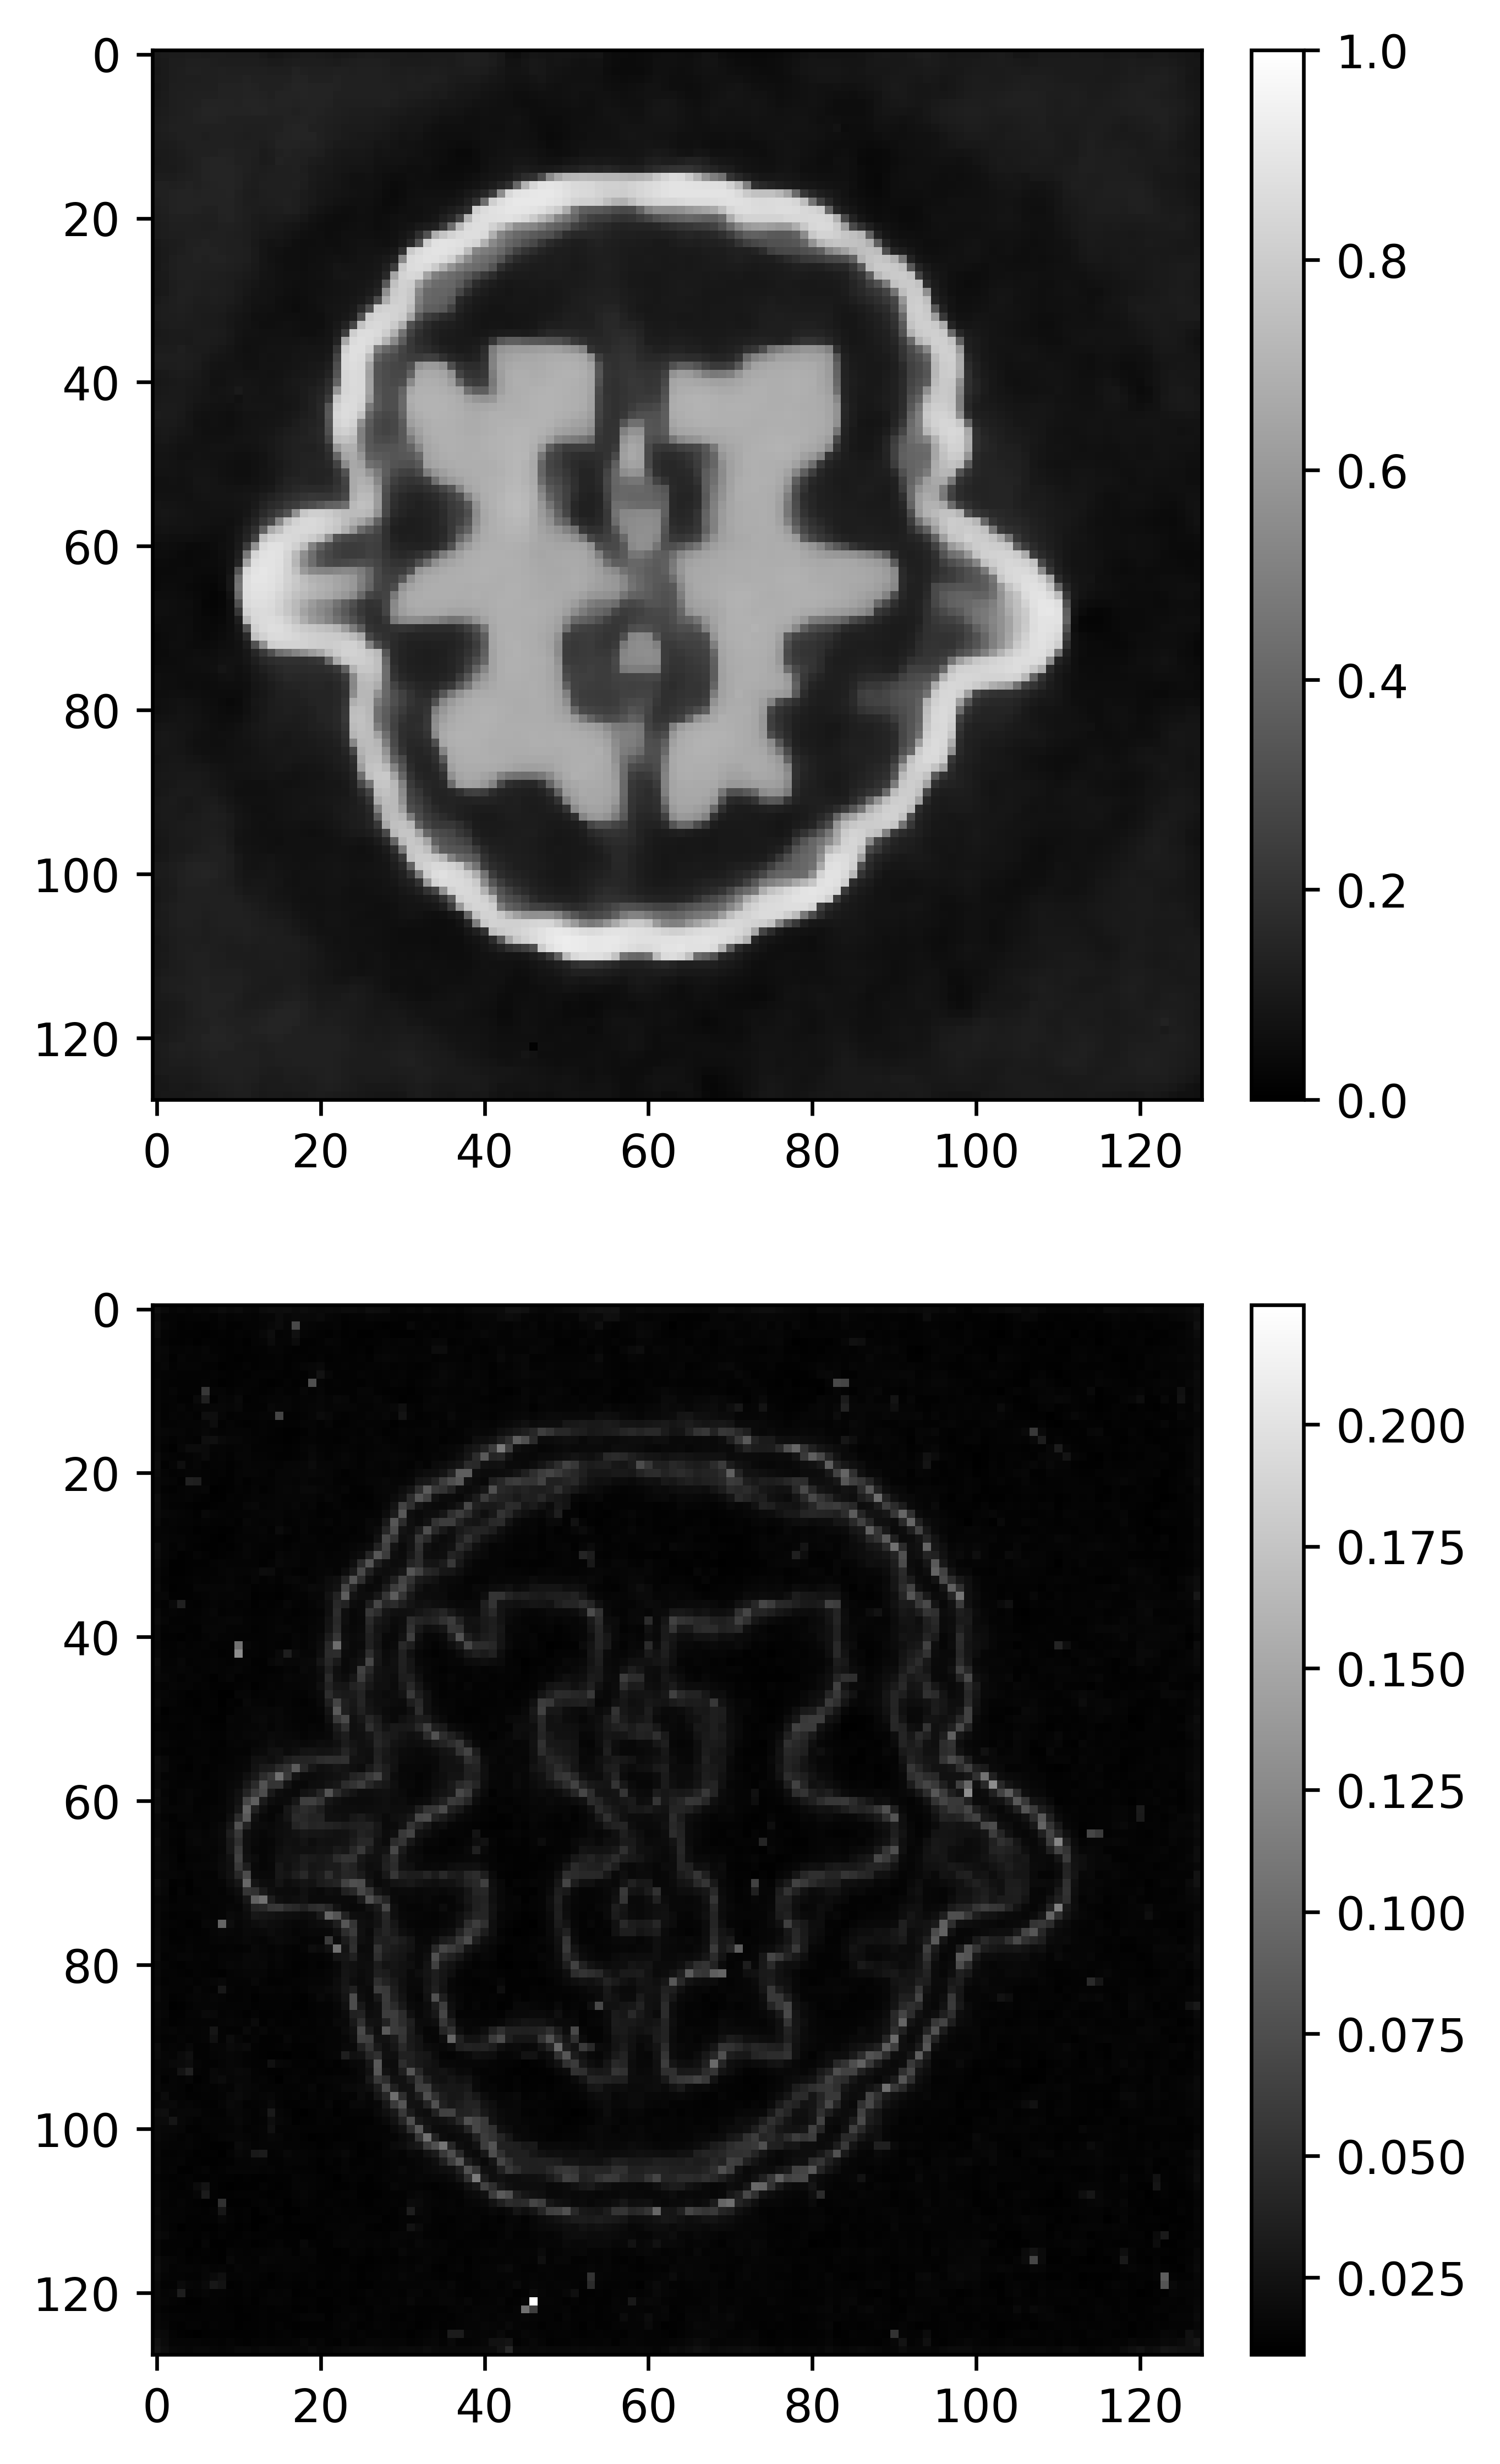

(d) pCN

Figure 5: Comparison of CT reconstruction for grains phantom with different priors. The upper images are posterior mean. The bottom images are posterior standard deviation.

The posterior mean and posterior standard deviation are shown in Figure 4 and Figure 5. Overall, for two small scale image problems, the fused L1/2L_{1/2} prior and the fused horseshoe prior have comparable performances in terms of both PSNR and SSIM. The images recovered by Total variation Gaussian prior always has the worst quality. The fused LASSO prior works reasonably well in Shepp–logan phantom. The main performance difference among all the algorithms is in Grains phantom, both the fused LASSO prior and the TV-Gaussian prior significantly fall behind. The fused L1/2L_{1/2} prior allows us to obtain a sharper reconstruction in Grains phantom, despite some of the grain features missing in the reconstruction and its PSNR is slightly lower than the fused horseshoe prior.

For uncertainty quantification, we observe that, all the posterior standard deviations are relatively large at the edge locations and almost zero in the rest of the image. Among all these priors, the posterior standard deviations based on the fused LASSO prior are particularly small in these two cases.

Refer to caption

(a) Gibbs-BPS

(b) Gibbs

(c) PLD